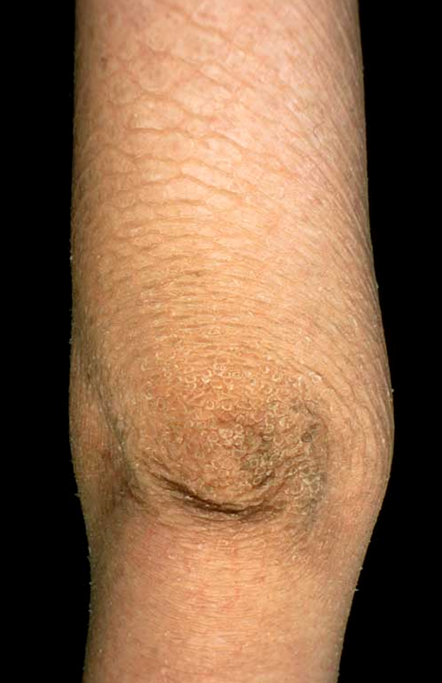

Name and briefly describe the condition shown

Steroid-sulphatase deficiency X-linked ichthyosis - a skin condition caused by the hereditary deficiency of the steroid sulfatase (STS) enzyme